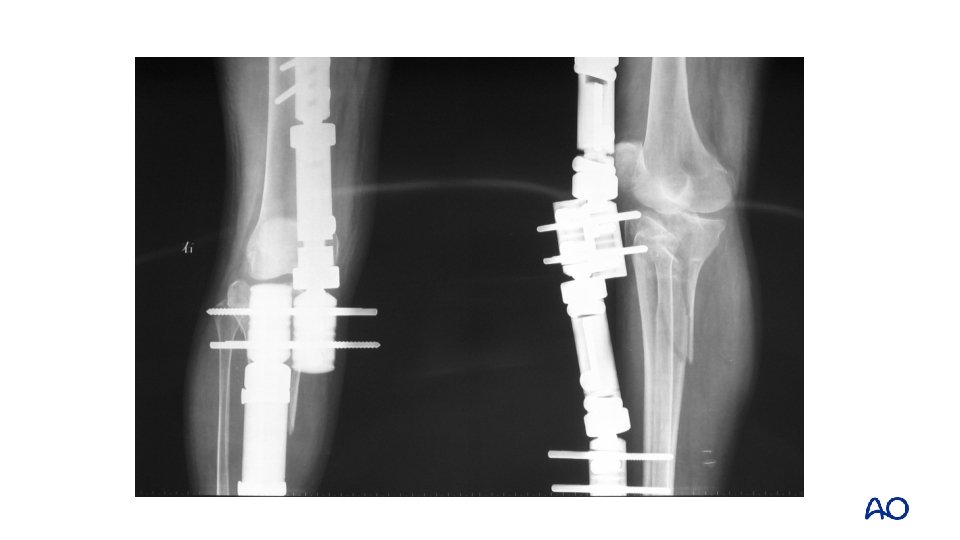

Fracture dislocation • More severe injury than other types of tibial plateau fractures

The result of ORIF for this type of injury is not satisfactory